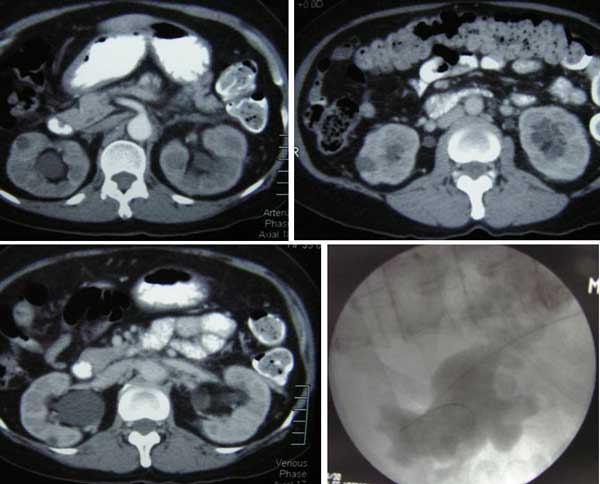

Pasien adalah seorang warnita berusia 56 tahun dari Medan, Indonesia. Pada Maret-April 2012, dia sakit perut diikuti dengan pendarahan. Dia mual dengan perutnya kembung. Dokter di Medan mendiagnosanya sebagai kanker serviks (leher rahim). Pasien datang ke rumah sakit swasta di Penang karena dia tidak bisa buang air kecil. Dia diberi tahu ini disebabkan karena pembengkakan ginjal nya. Sebuah kateter dipasang. Dia kemudian dirujuk ke dokter kandungan yang mengatakan bahwa kankernya telah menyebar ke kandung kemihnya.

Biopsi dilakukan. Laporan histopathologi mengatakan non keratinising squamous sel karsinoma. Pasien kemudian dirujuk ke onkolog. Dokter Onkologi menyarankan radioterapi. Pasien dan keluarganya menolak pengobatan dan kembali ke Medan. Pasien disuruh kembali ke Penang lagi setelah tiga bulan. Namun, setelah sebulan dan seminggu di rumah, pasien tidak bisa buang air kecil lagi. Masalah itu diselesaikan setelah kateter yang dipasang sebelumnya diganti. Namun demikian, pasien mengalami nyeri, mual dan muntah. Dia tidak bisa buah air besar selama lima hari terakhir dan kemudian buang air kecil nya diblokir lagi. Dokter harus ganti kateter untuk menyelesaikan masalahnya.